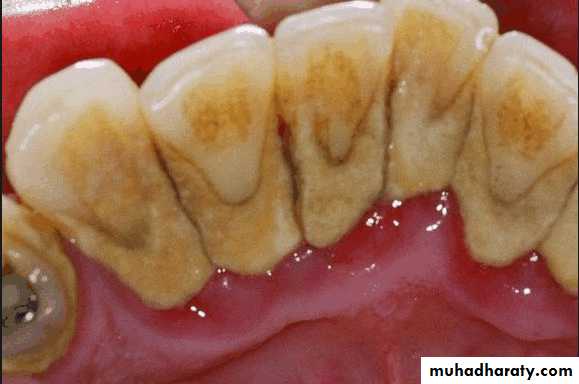

Oral prophylaxis

Supra gingival calculus should be removed and oral prophylaxis should be performed if these procedures have not been performed recently.

The diagnostic casts and the definitive intra oral examination will be more accurate if the teeth are clean.